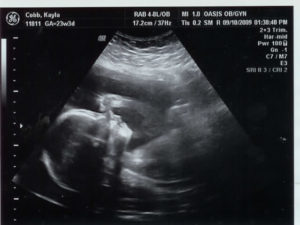

На УЗИ отчетливо виден малыш. Он шевелит ручками и ножками, иногда поворачивает лицо к аппарату. Так родители могут увидеть контуры личика. Обследование покажет, какую позицию он занимает и размеры плода.

На фото при проведении УЗИ мама может уже увидеть, как малютка улыбается, трет глазки и зевает, а также показывает язычок и пытается совладать с мимикой лица.

Зачастую на фото при проведении УЗИ запечатлена первая улыбка малютки и кулачок, уютно устроившийся под щечкой.Формирование нервной системы и мозга практически завершены, теперь малютка лучше владеет своим телом, он уже осознанно пытается пнуть ножкой мамин животик, пытается согнуть пальчики, а также ухватиться ими за пуповину.

Проводя УЗИ на таком сроке, можно с легкостью рассмотреть, как активно ведет себя малыш в утробе – двигается, кувыркается, трогает пуповину, играется руками и ногами.

В это время, помимо развития его органов, происходит строение костей.

На мониторе отчетливо видны его ногти и волосы, если они присутствуют, а также можно услышать биение сердца, которое не должно превышать 190 ударов в минуту.